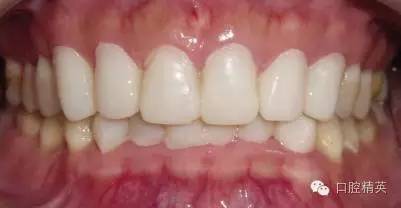

粘固后,對咬合關(guān)系進行初步調(diào)整。三天后,復(fù)查,進一步確認咬合關(guān)系,必要時進行調(diào)整(見圖12)。

LAVA 全瓷冠強度高,顏色自然,邊緣高度密合,切端可見半透明感,整體效果理想,與修復(fù)前(見圖1)相比取得了醫(yī)患均滿意的效果。